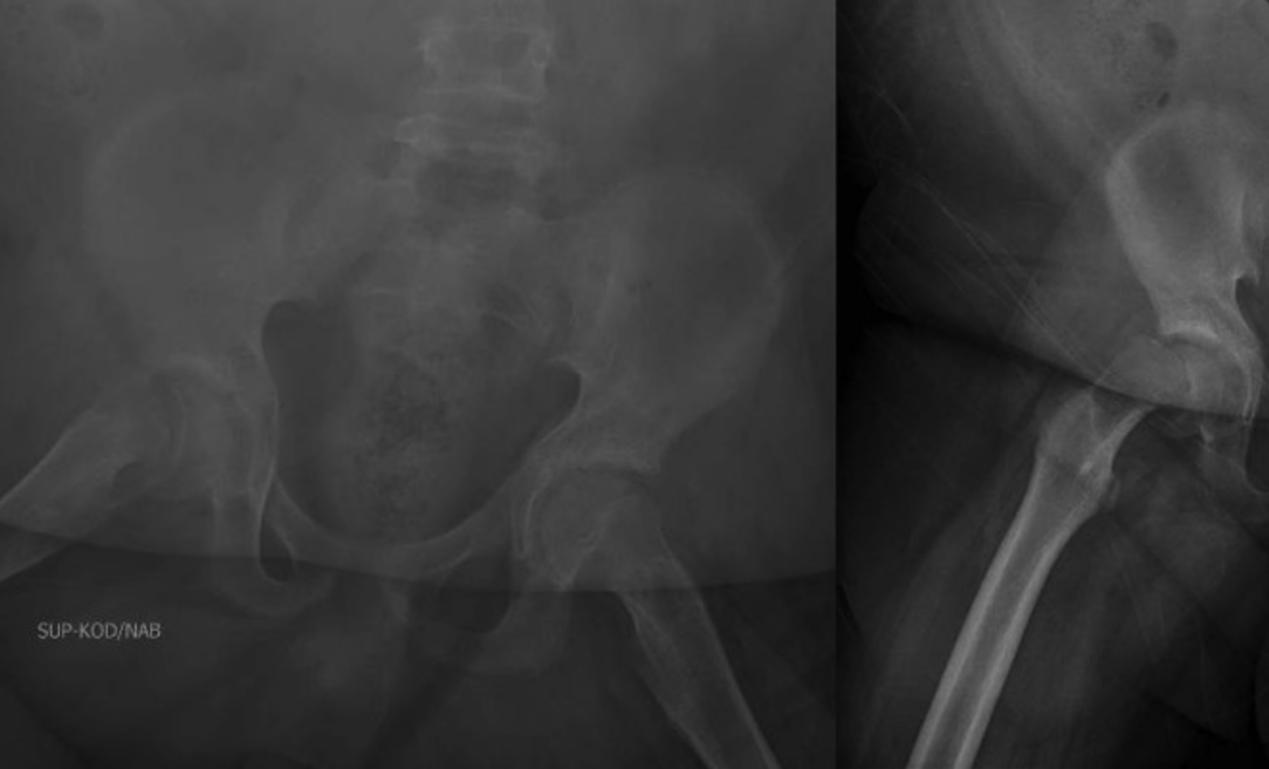

骨盆和右侧髋关节的x线片显示右侧SCFE,骺骨干角度(Southwick角)为75°(图1)。超声检查显示右侧髋关节积液(图2)。这些图像和检查证实患者目前诊断为急性严重不稳定的SCFE。病人在手术室进行了前Smith-Peterson入路,并进行了囊膜切开术,显示出有关节出血的情况。在干骺端前部轻轻按压复位。在干骺端放置两个空心螺钉以保持复位。对侧髋关节也被预防性固定非典型SCFE(图3)。

图1